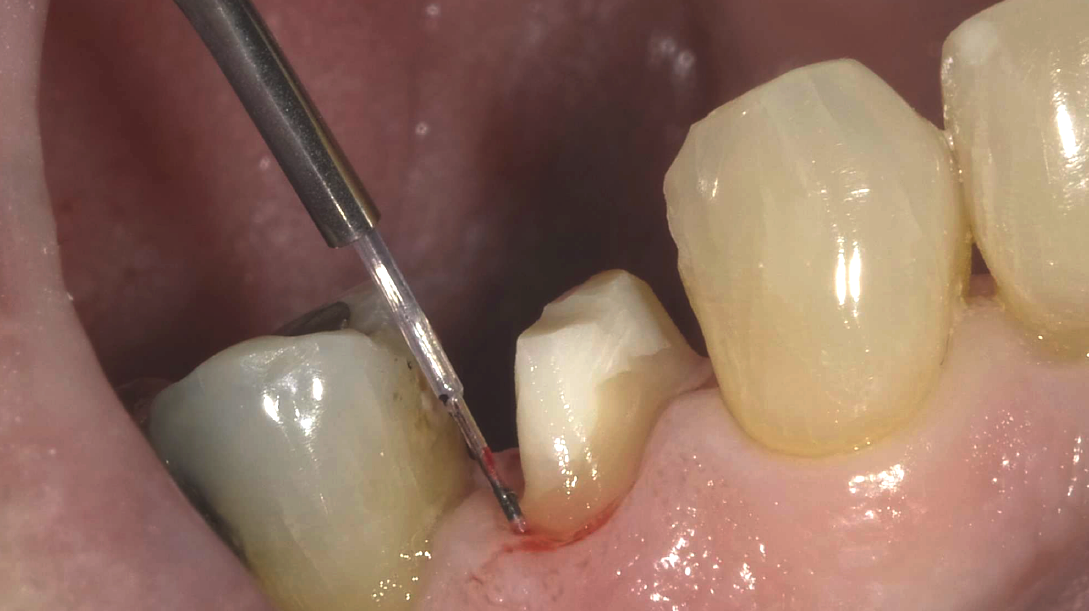

Don't be intimidated! Diode lasers are a great adjunct for direct and indirect restorative dentistry. In this On Demand Demonstration Webinar, join us as we simplify laser science, and show you a variety of situations where using a diode laser helps improve the final outcome. A step-by-step approach for complicated Class II restorations and a simplified approach to crown and bridge impressions and scans will leave you energized and ready to incorporate lasers into your practice.

- The complicated Class II - Tissue management, perfect contacts, and a beautiful outcome;

- Diode lasers in crown and bridge - From impression to insert;